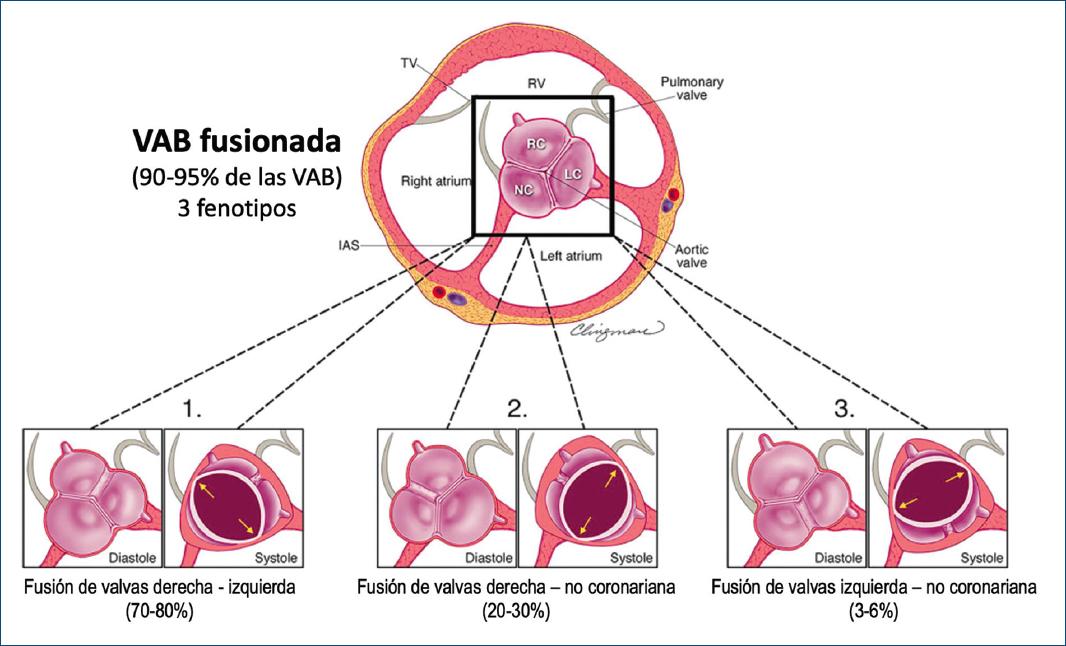

La VAB fusionada es la más común (Figs. 5 y 6) y representa aproximadamente el 90-95% de los casos de VAB2,28. La VAB fusionada se caracteriza por dos de las tres cúspides apareciendo fusionadas o unidas dentro de tres senos aórticos distinguibles, lo que resulta en dos cúspides funcionales (una fusionada o unida y la otra no fusionada) que generalmente son diferentes en tamaño y forma (Figs. 6-8), con ángulos comisurales de la cúspide no fusionado de diversos grados (Fig. 9). Comúnmente, los pacientes con una VAB fusionada demuestran una dominancia excéntrica del seno aórtico no fusionado y su cúspide (en comparación con los otros dos senos y dos cúspides fusionados), independientemente de la edad35 (Figs. 6 y 7). Con frecuencia (aproximadamente el 70%), pero no siempre (Fig. 8), se observa una cresta fibrosa congénita entre las cúspides fusionadas, denominada «rafé»28,36. La presencia de un rafé se ha asociado con la progresión de la disfunción valvular (particularmente estenosis aórtica) y la futura cirugía valvular26,36,37. Un rafé puede estar presente pero no ser visible inicialmente en el ecocardiograma y puede hacerse visible años después38.

Figura 6 Esquema de fenotipos de válvula aórtica bicúspide (VAB) fusionada vistos por la ecocardiografía transtorácica paraesternal de eje corto. Aplicable a vistas tomográficas similares por tomografía computarizada cardiaca y resonancia magnética cardiaca, la figura muestra los tres fenotipos de la VAB fusionadas como vistas ampliadas de la base del corazón (cuadrado negro) para la correlación anatómica de puntos de referencia. Nótese que todas las VAB fusionadas tienen tres senos aórticos distinguibles. Tenga en cuenta la apertura sistólica ovalada (forma de balón de fútbol americano) de estas tres válvulas en lugar de la apertura triangular de una válvula aórtica tricúspide. 1: fusión de la cúspide derecha-izquierda (más común) con rafé visible, dos cúspides funcionales de diferentes tamaños/formas (la cúspide no fusionada [no coronaria] es comúnmente de mayor tamaño «compensatorio» que las demás). 2: fusión derecha-no coronaria con rafé visible, dos cúspides funcionales de diferentes tamaños/formas (la cúspide no fusionada [izquierda] es más grande que las demás). 3: fusión izquierda-no coronaria (menos común) con un rafé visible, dos cúspides funcionales de diferente tamaño/forma (la cúspide no fusionada [derecha] es más grande que las demás). Es importante tener en cuenta que estas vistas de imágenes de eje corto no corresponden a la vista intraoperatoria del cirujano. Nótese cómo, en la diástole, el ángulo comisural de la cúspide no fusionada de estas tres VAB asimétricas es < 170-180° (Fig. 9); en sístole, las comisuras de la fusión derecha-izquierda son a las 10 y 4 en punto (1: flechas amarillas), las comisuras de la fusion derecha-no coronariana a la 1 y 7 en punto (2: flechas amarillas) y las comisuras izquierda-no coronariana a las 2 y 8 en punto (3: flechas amarillas) (Fig. 7). Estos tres fenotipos fusionados pueden no tener un rafé visible y también pueden tener un ángulo de cúspide no fusionada simétrico (Fig. 8) (modificada de Michelena et al., 20206 con permiso de Elsevier). RC: cúspide derecha; LC: cúspide izquierda; NC: cúspide no coronaria; RV: ventrículo derecho; TV: válvula tricúspide; IAS: septum interauricular.

Hay tres fenotipos específicos de VAB dentro del tipo fusionado: fusión de cúspide derecha-izquierda, fusión de cúspide derecha-no coronariana y fusión de cúspide izquierda-no coronariana (Figs. 4, 6 y 7). El fenotipo de fusión derecha-izquierda es el más común (70-80%)2,28,39. El fenotipo de fusión derecha-izquierda es también el acompañante más común de todas las variaciones de fenotipos aórticos (aorta normal, aorta ascendente dilatada, raíz dilatada, arco dilatado) y de la disfunción valvular (insuficiencia o estenosis). Aunque este fenotipo de fusión derecha-izquierda desarrolla estadísticamente más estenosis aórtica2, se ha asociado en algunos pacientes40,41 con dilatación de la raíz aórtica, insuficiencia aórtica y preponderancia masculina (estas asociaciones se han denominado el «fenotipo de raíz»)38,39. La fusión derecha-izquierda también está fuertemente asociada con coartación aórtica en niños42.

El fenotipo de fusión derecha-no coronariana es el siguiente más común (20-30%). Se asocia con una mayor prevalencia de estenosis aórtica en adultos37 y también predice de forma independiente la progresión de la insuficiencia aórtica en adultos33. Del mismo modo, el fenotipo de fusión derecha-no coronariana se asocia con una progresión más rápida de la estenosis aórtica y la insuficiencia en niños y adolescentes42,43. El fenotipo de fusión izquierda-no coronariana es el fenotipo menos común (3-6%) en todos los estudios.